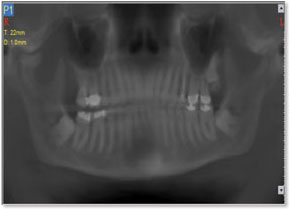

The CT scan of the right TM Joint produced a startling revelation. A large boney projection extended from the anterior condylar neck of the mandible superiorly, like a tree trunk, and mushroomed up to the opposing articular eminence. A 3-D projection showed the growth wrapped from posterior, to beneath, and even anterior to the articular eminence. This explained the inability to translate upon opening. A panoramic view also clearly showed the hard tissue pathological projection, which extended vertically beyond the height of the mandibular condyle, thus producing a resulting right side open bite. The diagnosis was quickly clarified through CBCT technology.